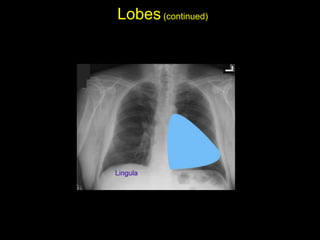

The document discusses the anatomy of the chest x-ray and CT scan by describing the lobes of the lungs and their locations. It also mentions the heart, mediastinum, hilum, and ribs. Several axial, coronal, and sagittal CT images are included with labels pointing out structures like the trachea, bronchi, lobes of the lungs, and fissures. In summary, the document provides an overview of lung and chest anatomy as seen on x-rays and CT scans through text descriptions and labeled medical images.